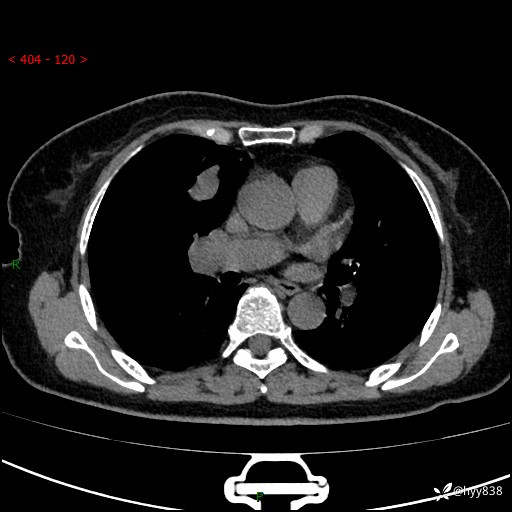

【患者信息】:70岁/女

【主诉】:发现右上肺肿物10天

【现病史及既往史】:者10天前因“背部酸痛”于当地治疗,无发热,无呕吐,无头痛头晕等不适,胸部CT示右上肺肿物。遂来我科就诊,门诊看过病人后以“”收入我科, 自患病以来,精神、饮食、睡眠尚可,大小便正常,体力体重无明显减轻。

【检查】:胸部CT平扫(患者过敏体质,不能增强)